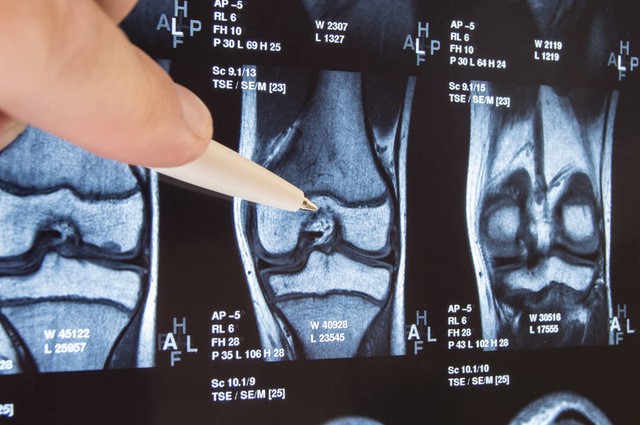

关节疼痛可能是关节炎、关节损伤或其他关节问题的症状,只有通过专业的诊断和治疗,才能有效预防和治疗关节问题。

6. 规律就医:定期进行体检,及早发现和治疗与关节相关的问题,如骨质疏松症、关节炎等。